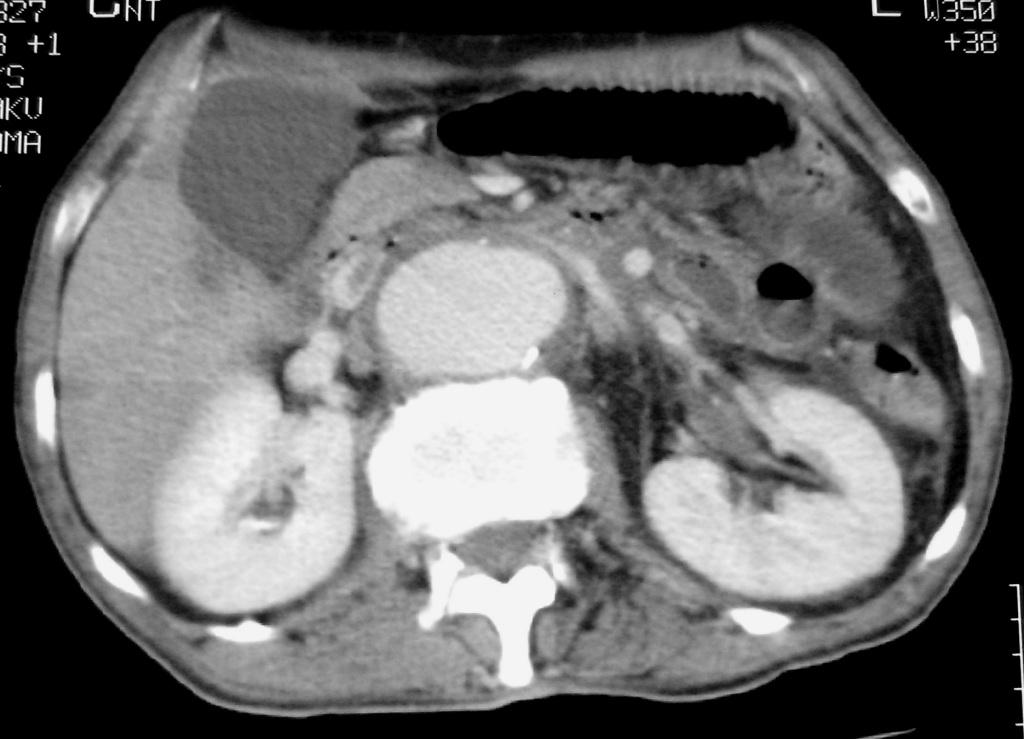

We describe the case of a 60-year-old diabetic man who was admitted to our hospital with keto-acidosis and rapidly developed sepsis and a mycotic abdominal aortic aneurysm (AAA) with branch involvement. Early and late findings on serial computed tomography (CT) examinations are presented. Awareness and recognition of early imaging findings associated with infectious aortitis and serial CT examination in cases of patients with sepsis and predisposing factors are essential for prompt diagnosis and treatment.